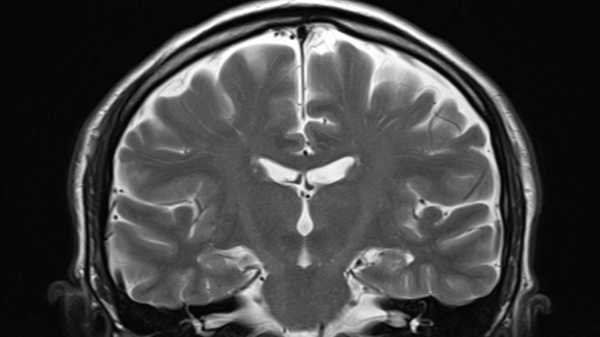

A new study shows that repeated head impacts of any intensity over time may increase the risk of developing chronic traumatic encephalopathy. (Image credit: Klaus Wedfelt/Getty Images)